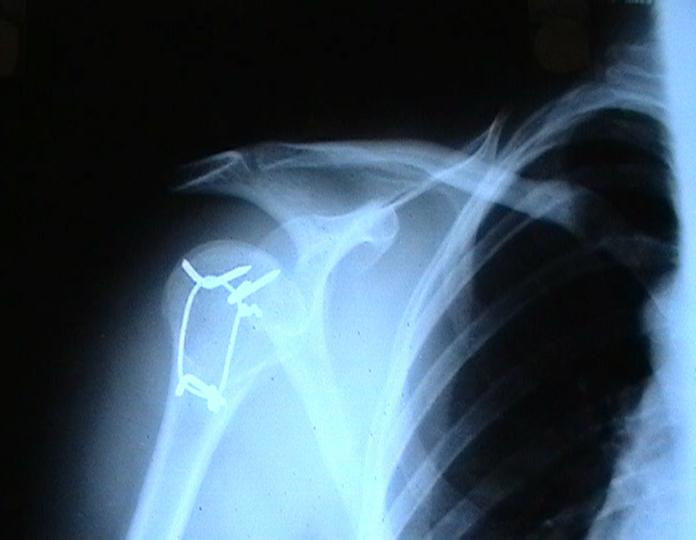

Переломовывих плеча сложная проблема и технически не уверен как для коллег, но для меня сколько я не встречался, технически сложно *вытянуть* вывихнутую головку из-под впадины. Последнее время не применяю пластины для фиксации перелома, а использую спицы и проволочную петлю (тем более часто и густо спонгиозные винты не держатся в головке прочно).